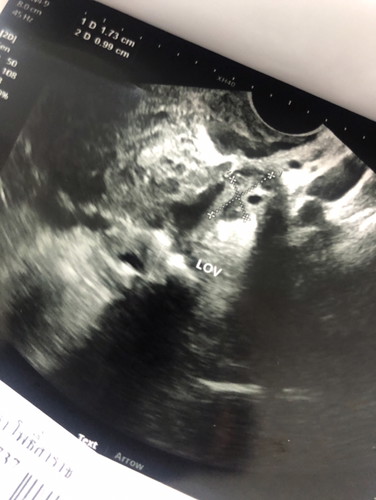

เรื่องมีอยู่ว่า เมื่อวานเรา ซื้อที่ตรวจครรภ์มาตรวจ สรุปขึ้น 2ขีด เราบอกสามี ต่างพากันดีใจ เพราะรอน้องมานานมากแล้ว เลยตัดสินใจ ไปฝากครรภ์พิเศษที่คลีนิค ฝากครรภ์ ช่วงเย็นเราเริ่ม หน่วงท้อง นิดเดียว ตกกลางคืน เริ่มปวดพอทนไหว พอเช้า 9 โมง 40 นาที เรา มีเลือดไหลออกช่วงคลอด เป็นประจำเดือนเราตกใจมาก เพราะอายุครรภ์เราแค่ 4 สัปดาห์ เลย ตัดสินใจไปโรงพยาบาล เจาะเลือด อัลตร้าซาวด์ ตรวจปากมดลูก จรวจทุกอย่างเสร็จเรียบร้อย คือ น้อง ยังอยู่ แต่เลือดไหลไม่หยุด มีโอกาสเสี่ยงแท้งได้ อีกอย่าง ฮอร์โมนที่ตรวจได้ ได้แค่ 65 ตอนนี้ หมอให้กลับมาพักที่บ้าน แต่เลือดไหลไม่หยุด หมอบอก น้องอาจจะหลุด ให้รอดูอาการ หมอนัด อัลตราซาวด์ ดูน้อง อีกที อาทิตย์หน้า เราเสียใจมาก เพราะพึ่งรู้ว่าน้องมาแล้วแค่1วัน ทำยังไง เราไม่อยากเสียน้องไป ยาวหน่อยอย่าว่ากันนะคะคุณแม่ๆ